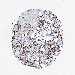

BRCA TCGA BRCA VALIDATION PROTEIN EXPRESSION